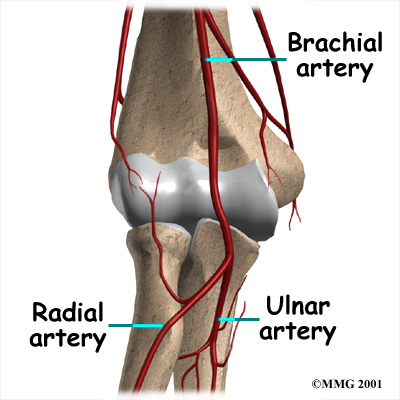

Blood Vessels

Traveling along with the nerves are the large vessels that supply the arm with blood. The largest artery is the brachial artery that travels across the front crease of the elbow. If you place your hand in the bend of your elbow, you may be able to feel the pulsing of this large artery. The brachial artery splits into two branches just below the elbow: the ulnar artery and the radial artery which both continue into the hand. Damage to the brachial artery can be very serious because it is the only blood supply to the hand.